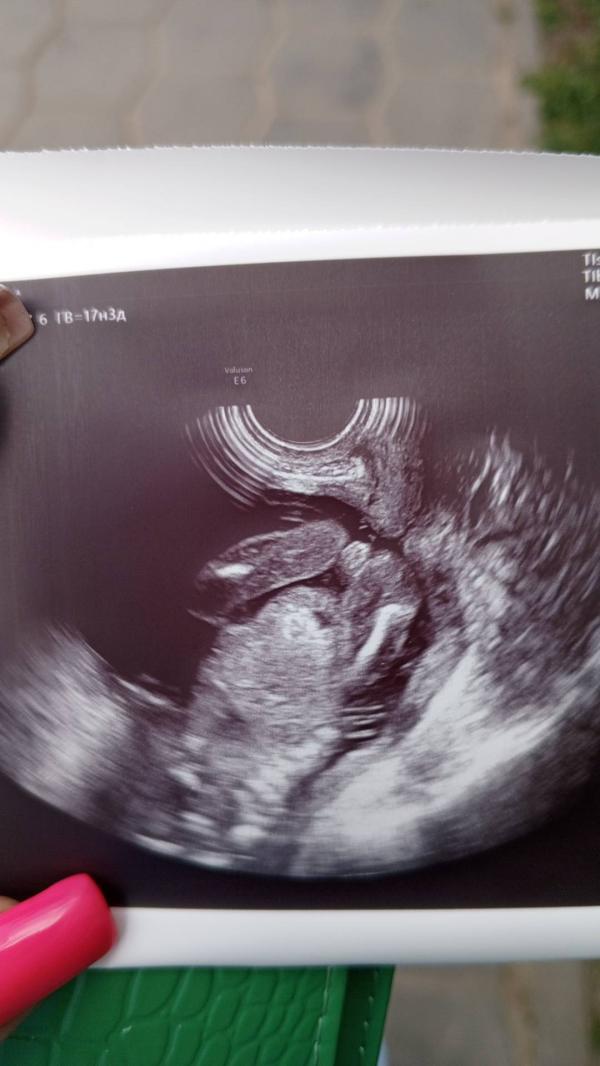

Девочка или нет?

Сходила на узи сказали что девочка, да вот не понимаю, точно ли это девочка? 😅

И не рано ли я пошла для определения пола?